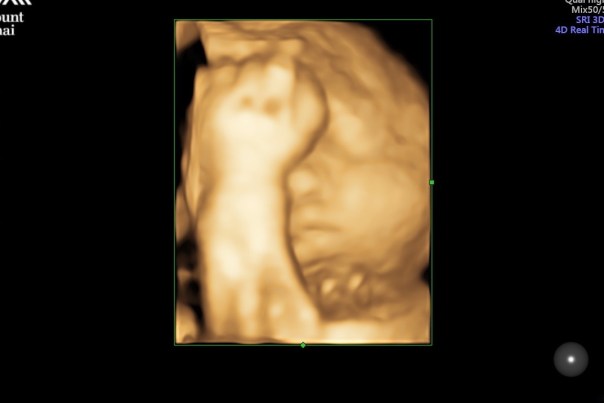

. After all, it was my first time getting pregnant, I had no fucking clue what to expect or what the process TRULY entailed, so yeah, I wanted to do the thing I was told is “optimal.” No-brainer here. Do the “optimal, ideal” thing, because those are strong words that sound good. And I’m gonna be a good mom, damnit!

(<— definitely what post-labor looks like, no?)